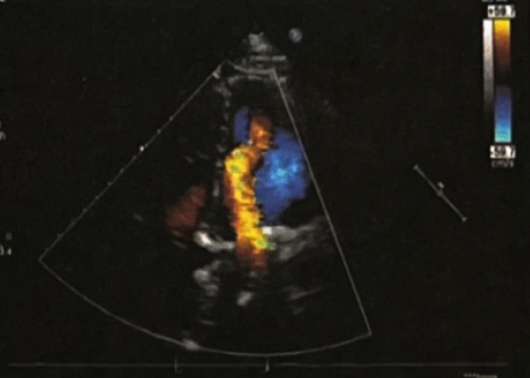

患者行胸部CT(图3)显示右肺下叶节段性膨胀不全,未见气胸表现,同时可见双侧胸腔少量积液,心影增大不明显,暂排除肺部感染、气胸、心力衰竭疾病,X线胸片(图4)提示右侧膈肌上抬,透视检查可见右侧膈肌抬高,运动幅度明显减弱(图5)。常见引起膈肌抬高的常见原因有:①肝脏占位、脓肿;②肺不张引起肺容积缩小;③膈肌麻痹。结合此患者房颤消融史,考虑可能为房颤射频消融术引起了膈神经损伤,然后出现了膈肌麻痹。

(4).png)